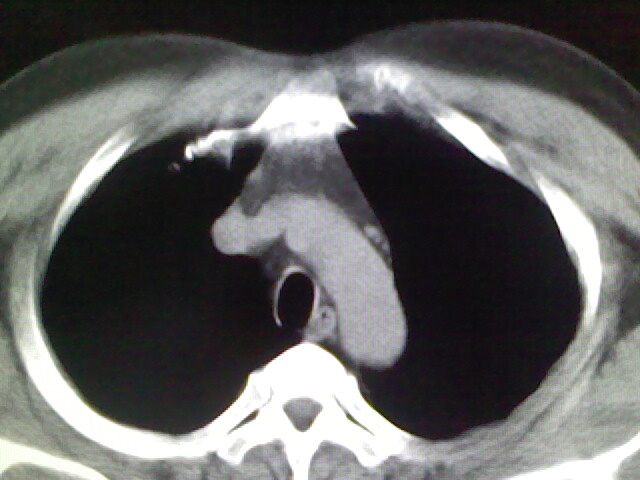

标题: CT17932:临床怀疑肺栓塞

男,34岁,自觉右侧胸痹,胸闷3天余

右侧肺动脉似见密度稍低影,请在机器的薄层上再看看有没有充盈缺损。